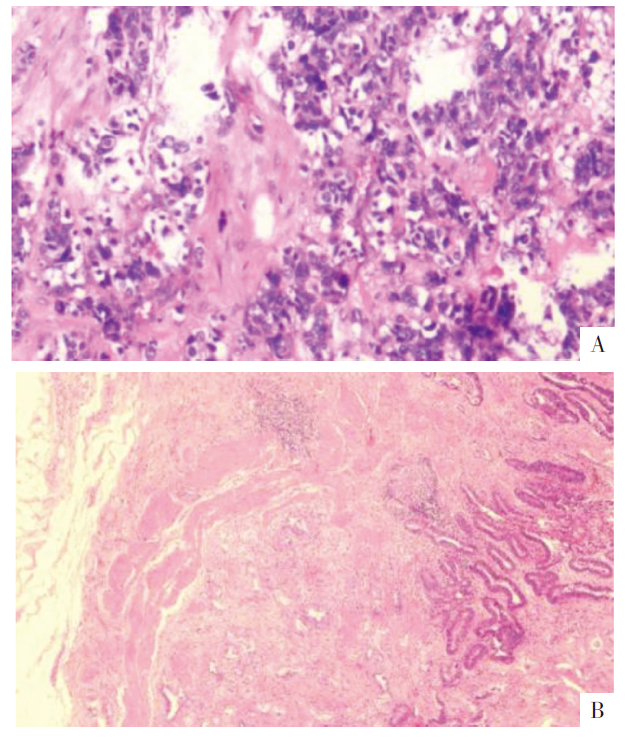

• 图5 胆囊术后病理图。A图为大细胞神经内分泌癌,B图为中分化腺癌(HE,×400)。